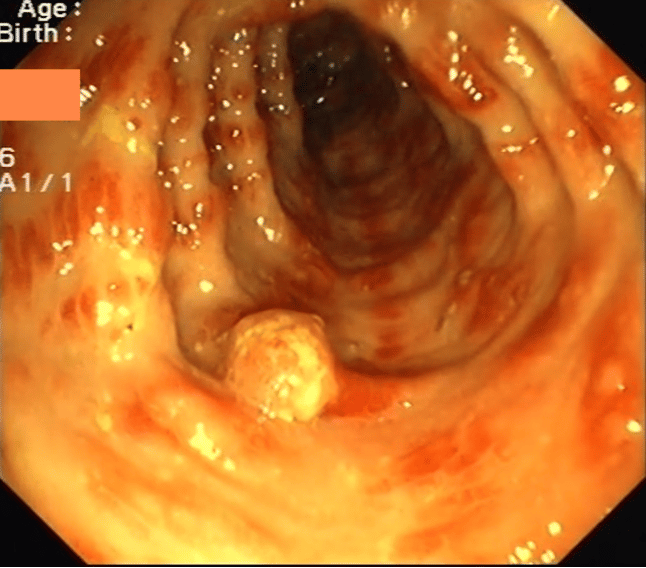

Colonoscopy showed multiple reddish, edematous mucosal streaks and polyps and pseudopolyps ranging from 5 to about 20 mm. On EGD the stomach was characterized by enlarged mucosal folds, pseudoplyps and duodenal mucosal atrophy. Histology showed the above findings (see figure 2).